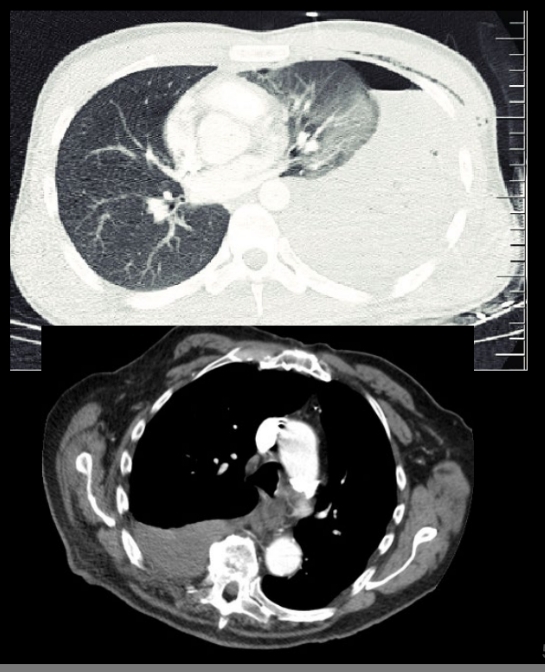

Mejor estudio para ver hemotórax

TC

- Se ve el derrame denso